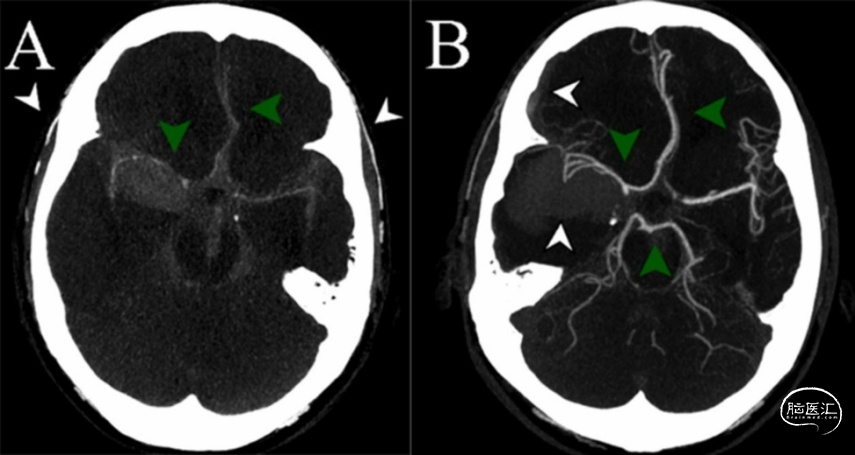

动脉瘤性蛛网膜下腔出血(aSAH)患者约有25%死于院前或急诊室。SAH引起的猝死第一症状是意识丧失(loss of consciousness,LOC),这也是非致命性SAH的常见症状。对动脉瘤破裂时LOC的病理生理机制仍有争议。芬兰赫尔辛基大学神经外科的Ilari Rautalin等在2021年2月的《Neurocrit Care》杂志报道1例aSAH患者在没有心脏停止搏动的情况下,出现短暂的颅内循环停止而意识丧失;这种颅内循环停止是短暂的,伴临床状态不佳,但可以恢复较好。1例有吸烟史、高血压和哮喘的50-60岁患者在运动时意识丧失,接受复苏后患者在几分钟内意识恢复。入院时患者神志清醒,无神经功能缺失,但血压偏高和头痛严重。进行CT检查时,患者再次意识丧失,并出现窦性心动过缓,但瞳孔大小及光反射正常。即刻气管插管,行头部CT扫描和CTA检查。在CTA检查期间,收缩压突然升高超过200mmHg。给予镇静和抗高血压药物治疗,双侧瞳孔变大、光反射消失。CTA成像显示,大脑中动脉近端和大脑前动脉水平远端的颅内循环停止,但颅外动脉正常充盈(图1a)。CT扫描示弥漫性SAH合并脑内血肿,未发现颅内动脉瘤。快速输注甘露醇后,患者瞳孔在10分钟内恢复正常。在第一次CTA的57分钟后患者状态稳定,再次CTA检查显示颅内循环恢复(图1b),并有再出血迹象,右后交通动脉处有可疑病灶。接着,DSA检查发现,右侧后交通动脉瘤(图2a)。住院期间的心电图和生物标志物均未提示发生过应激性心肌病。给予显微手术夹闭动脉瘤(图2b),并清除脑内和硬膜下血肿。患者出现脑积水,采用脑室腹腔分流术。一年后,患者重返工作岗位,并进一步进行神经认知后遗症的康复治疗。

图1. 患者在发生aSAH时行CT扫描和CTA成像。A.动脉瘤破裂、颅内循环停止,大脑前、中动脉远端区域充盈模糊(绿色箭头),而颅外动脉清晰可见(白色箭头)。B.颅内循环恢复后,大脑前、中、后动脉供血区正常充盈。CTA提示再次出血(白色箭头)。